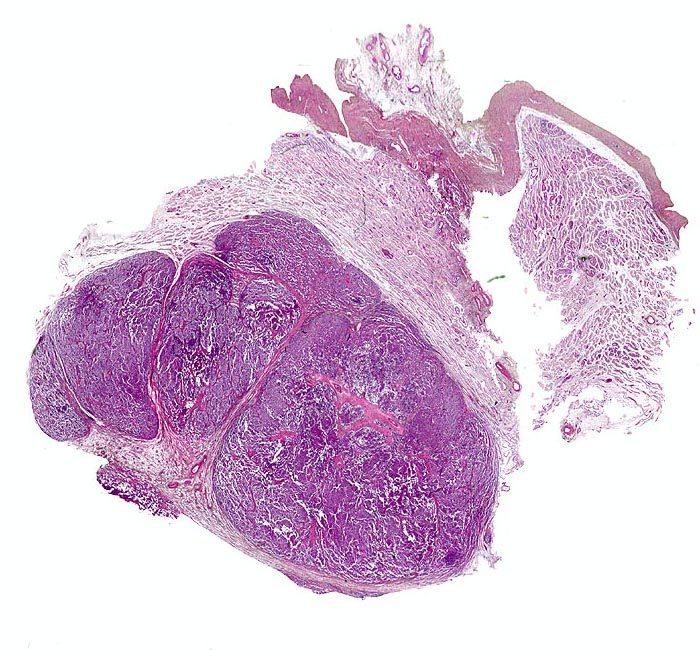

Makroskopisch imponieren Seminome als gut begrenzte weiche crèmefarbene Knoten oder diffuses Intiltrat. Mikroskopisch findet sich eine uniforme Population grosser Zellen mit prominentem zentralem Nukleolus, welche durch schmale Bindegewebssepten voneinander getrennte Nester bilden. Ein leukozytäres Entzündungsinfiltrat, synzytiotrophoblastäre Riesenzellen und Mikroverkalkungen können zusätzlich vorhanden sein. Gelegentlich induziert der Tumor eine ausgeprägte granulomatöse Entzündung. Dies kann zur Fehldiganose einer granulomatösen Orchitis führen.

• Scharf begrenzter Tumorknoten mit eosinophilen Nekrosearealen.

• Unterschiedlich breite solide Tumorzellstränge aus monomorphen Zellen mit grossen hyperchromatischen Kernen und einem solitären zentralen prominenten Nukleolus. Reichlich helles Zytoplasma mit scharfen Zellgrenzen.

• Schmale bindegewebige Septen mit Kapillaren und lymphoplasmazellulärem Entzündungsinfiltrat.